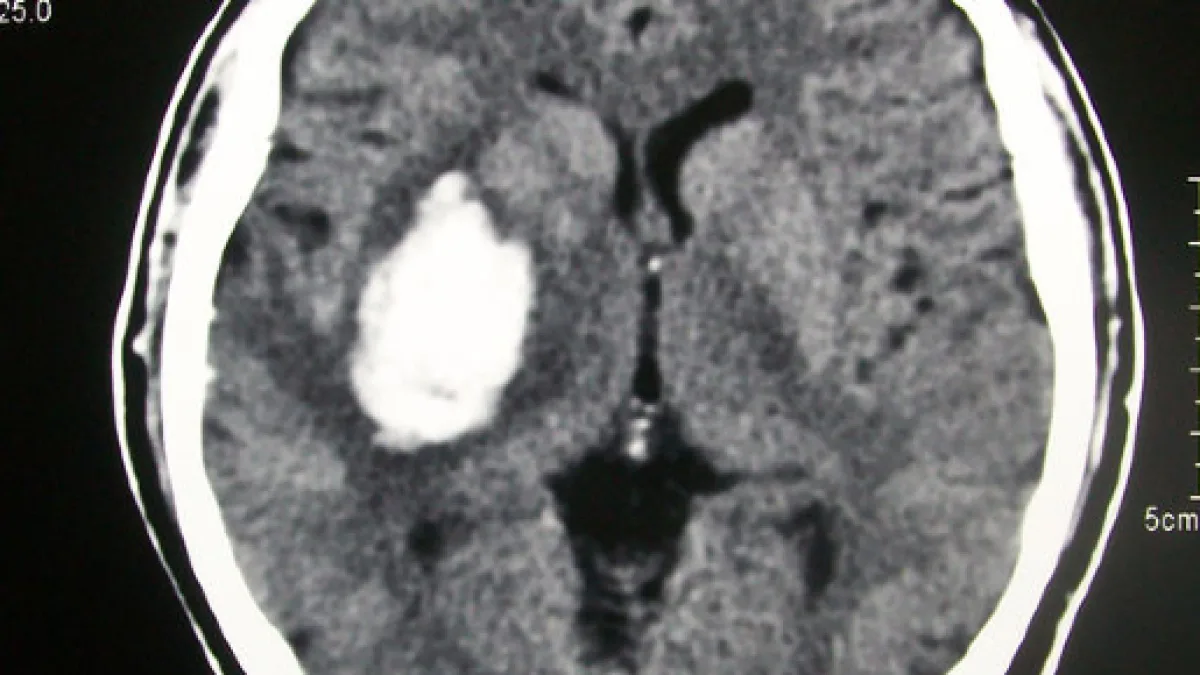

Sembrava davvero essere stato tutto fatto a regola d'arte, se non fosse che al momento dell'inizio dell'esame sullo schermo è stato possibile notare come la paziente fosse riuscita ad accedere nel macchinario per la tomografia computerizzata con un telefono cellulare.

La macchina ovviamente ha provveduto a registrare le fasi in cui la donna ha risposto al telefono e, considerato anche il fatto che sono stati scongiurati pericoli, è stato possibile rendere pubblica la singolare immagine. Una sorta di monito attraverso cui probabilmente da parte dell'Ospedale c'è stata voglia di raccontare al mondo quanto una cosa così singolare, a tratti divertente, avesse in realtà potuto portare a conseguenze ben peggiori. A rendere ancor più dolce la vicenda c'è la notizia che l'esame è stato poi ripetuto e la signora ha potuto avere contezza del fatto che nessuna patologia neurologica fosse la causa di quel mal di testa.